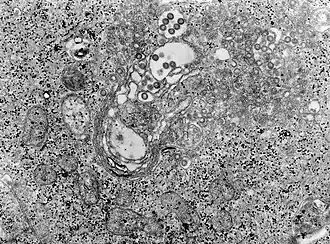

Rift Valley: Фотография ткани под микроскопом инфицированной вирусом лихорадки